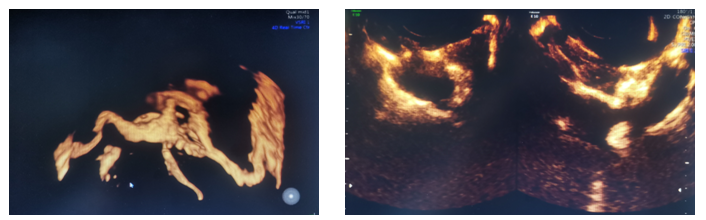

患者为31岁不孕症女性,在西咸院区产科就诊后,临床医生接诊后认为需要超声检查以评估宫腔情况及双侧输卵管通畅性。超声诊断中心任媛主治医生全程配合,为患者行四维超声宫腔成像及输卵管超声造影检查,整个过程顺利,耗时短,患者无不适,该项检查为临床及患者提供了客观影像学信息。

输卵管超声造影检查是通过向宫腔内注射超声造影剂,使宫腔及输卵管显影,可清楚观察到宫腔、宫角、双侧输卵管的形态及与卵巢的位置关系,黑料网西咸院区超声诊断中心已具备实施该项检查的设备及技术支持。子宫输卵管超声造影技术的成功开展,为产科不孕不育专科门诊发展提供了可靠的超声检查技术支撑,大大方便了西咸新区不孕患者的检查和治疗,助力西咸新区生殖技术等相关专业发展的推进和提升。